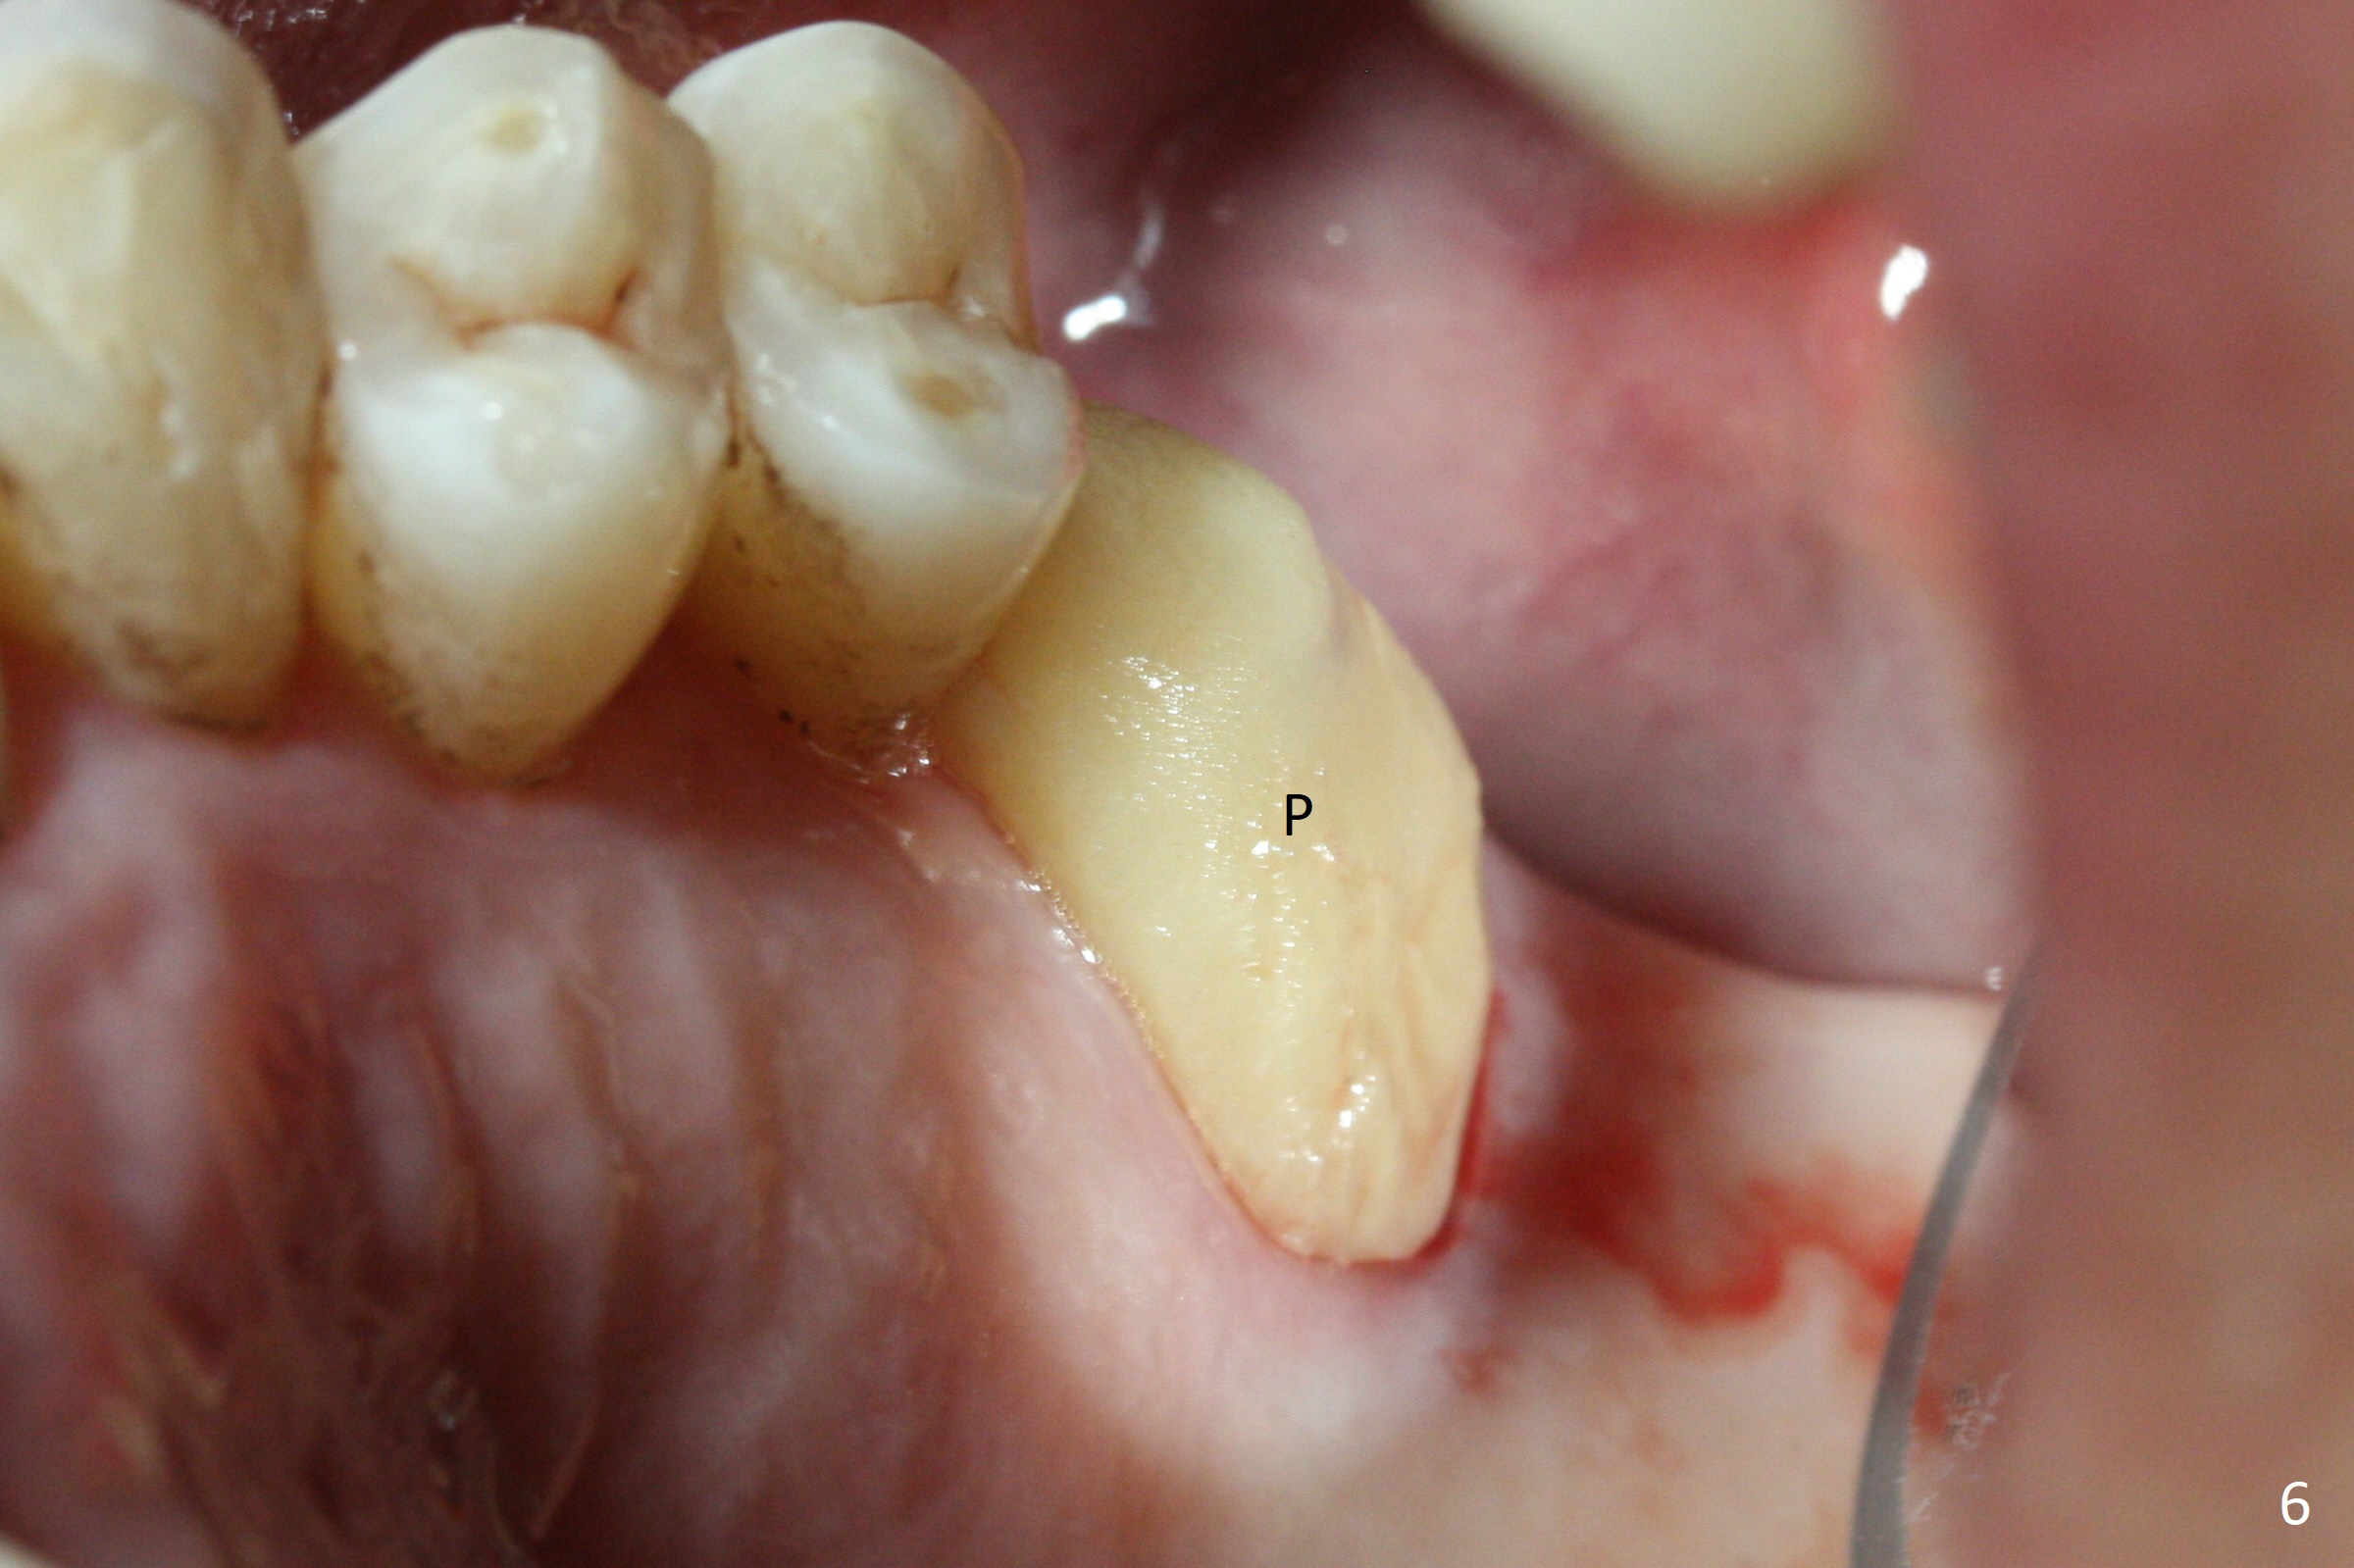

Buccal gingival recession at #14 (Fig.1) is less severe than the palatal one (Fig.2).  Without raising the buccal gingiva (Fig.3 B), osteotomy in the septum is established apparently in the middle socket (Fig.3 *, 4).  As the osteotomy increases with 3.8 mm drill, the palatal wall of the osteotomy starts to be perforating.  When a 4.5x11.5 mm implant is placed, palatal threads are exposed, to which autogenous bone and Vera Graft are placed (Fig.5 *).  After placement of a 5.5x5(3) mm abutment, an immediate provisional (Fig.6 P) is fabricated to cover the sockets.  If the septal dimension were studied carefully by raising the buccal gingiva slightly, the osteotomy could be initially more buccal so that the palatal thread exposure could be less.  When the provisional is removed 1.5 months postop, the implant is exposed palatally.  The margin of the provisional is modified so that the implant can be cleaned by the patient using Water Pik.  In fact, the healthy gingiva seems to be attached to the implant threads 2 weeks later (Fig.7).  The distal implant threads remains exposed 6 months postop; it appears that the distal socket wall has resorbed (Fig.8).  The sockets heal 1 year 7 months post cementation (Fig.9).